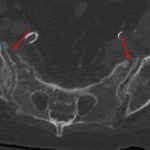

- Acute bilateral vertically-oriented sacral insufficiency fractures

- Sacral insufficiency fractures

Acute bilateral vertically-oriented sacral insufficiency fractures.